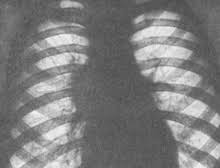

- Рентгенография грудной клетки – как альтернатива, может проводиться компьютерная томография.

При рентгенологическом обследовании врач увидит в органах дыхания патологические образование – мелкие очаги воспаления в виде гнойничков и гранулем. Бронхоаденит характеризуется на снимке при рентгенографии изменением формы корня легкого, его деформацией, расширением или искривлением. Изменения крови аналогичны определяемым при острой туберкулезной инфекции. На основании клинических и рентгенологических проявлений врач делает заключение и ставит корректный диагноз, после чего подбирает оптимальную схему лечения.